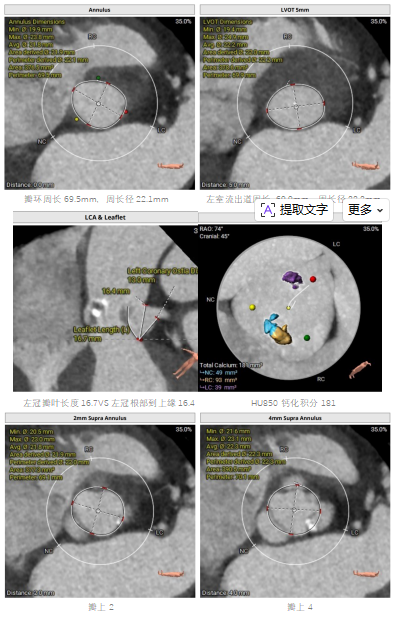

为确保手术安全有效,术前,团队为患者进行了精细的心脏CTA扫描,并运用先进的三维重建技术,对患者的主动脉根部解剖结构、瓣膜钙化程度、冠状动脉开口位置及入路血管条件进行了全方位、立体化的“术前推演”。

评估结果极其复杂:患者为功能性二叶瓣,R-N交界高位融合,瓣叶增厚伴重度钙化,钙化主要分布于右无窦交界区,左室流出道呈直筒型,瓣膜锚定难度较大,术中面临瓣膜移位、瓣周漏、冠状动脉阻塞等多重风险。心血管内科团队联合心外科、影像科、超声科、麻醉科、体外循环科、介入导管室等多学科专家,基于患者病情及CTA精确测量结果,术前联合分析并制定了详细的手术策略,包括手术流程及释放技巧、左冠保护方案以及循环崩溃的应急预案。

血管外周及入路评估

外周入路少许钙化斑块,入路良好